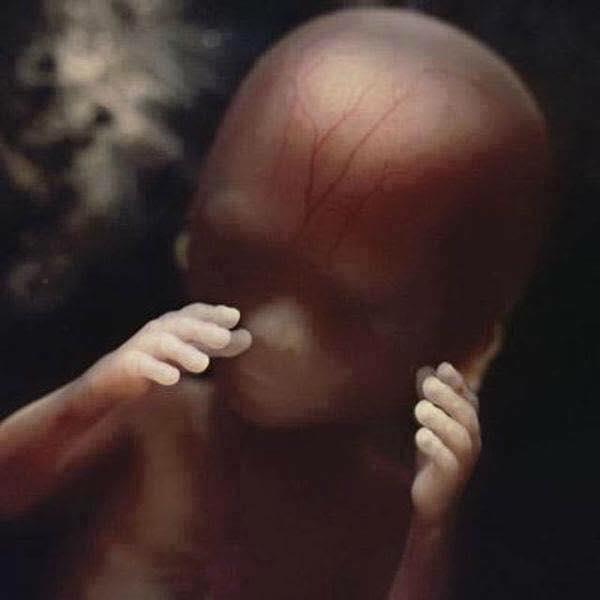

8 semanas, embrião crescendo protegido pela bolsa fetal.

12 semanas